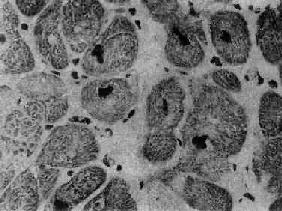

镜下,心肌细胞显著肥大,核大而浓染(图8-36),核周有亮区包围,组织化学染色证明为糖原堆积,具有一定的诊断意义。心肌细胞排列紊乱较其它型心肌病为甚,而且常呈旋涡状或缠绕呈簇状排列(图8-37),细胞内肌原纤维不呈平行排列,而是向各个方向、互相交错排列。常有间质纤维化灶形成,但以内膜纤维化,尤其位于主动脉瓣下区的内膜纤维化为突出。位于肥厚的室间隔内的冠状动脉分支管壁常有增厚现象。

图8-36 肥厚性心肌病

心肌细胞肥大,核大浓染 (采自Edwards)

图8-37 肥厚性心肌病

心肌细胞排列紊乱 ×180(原放大)(采自Edwards)